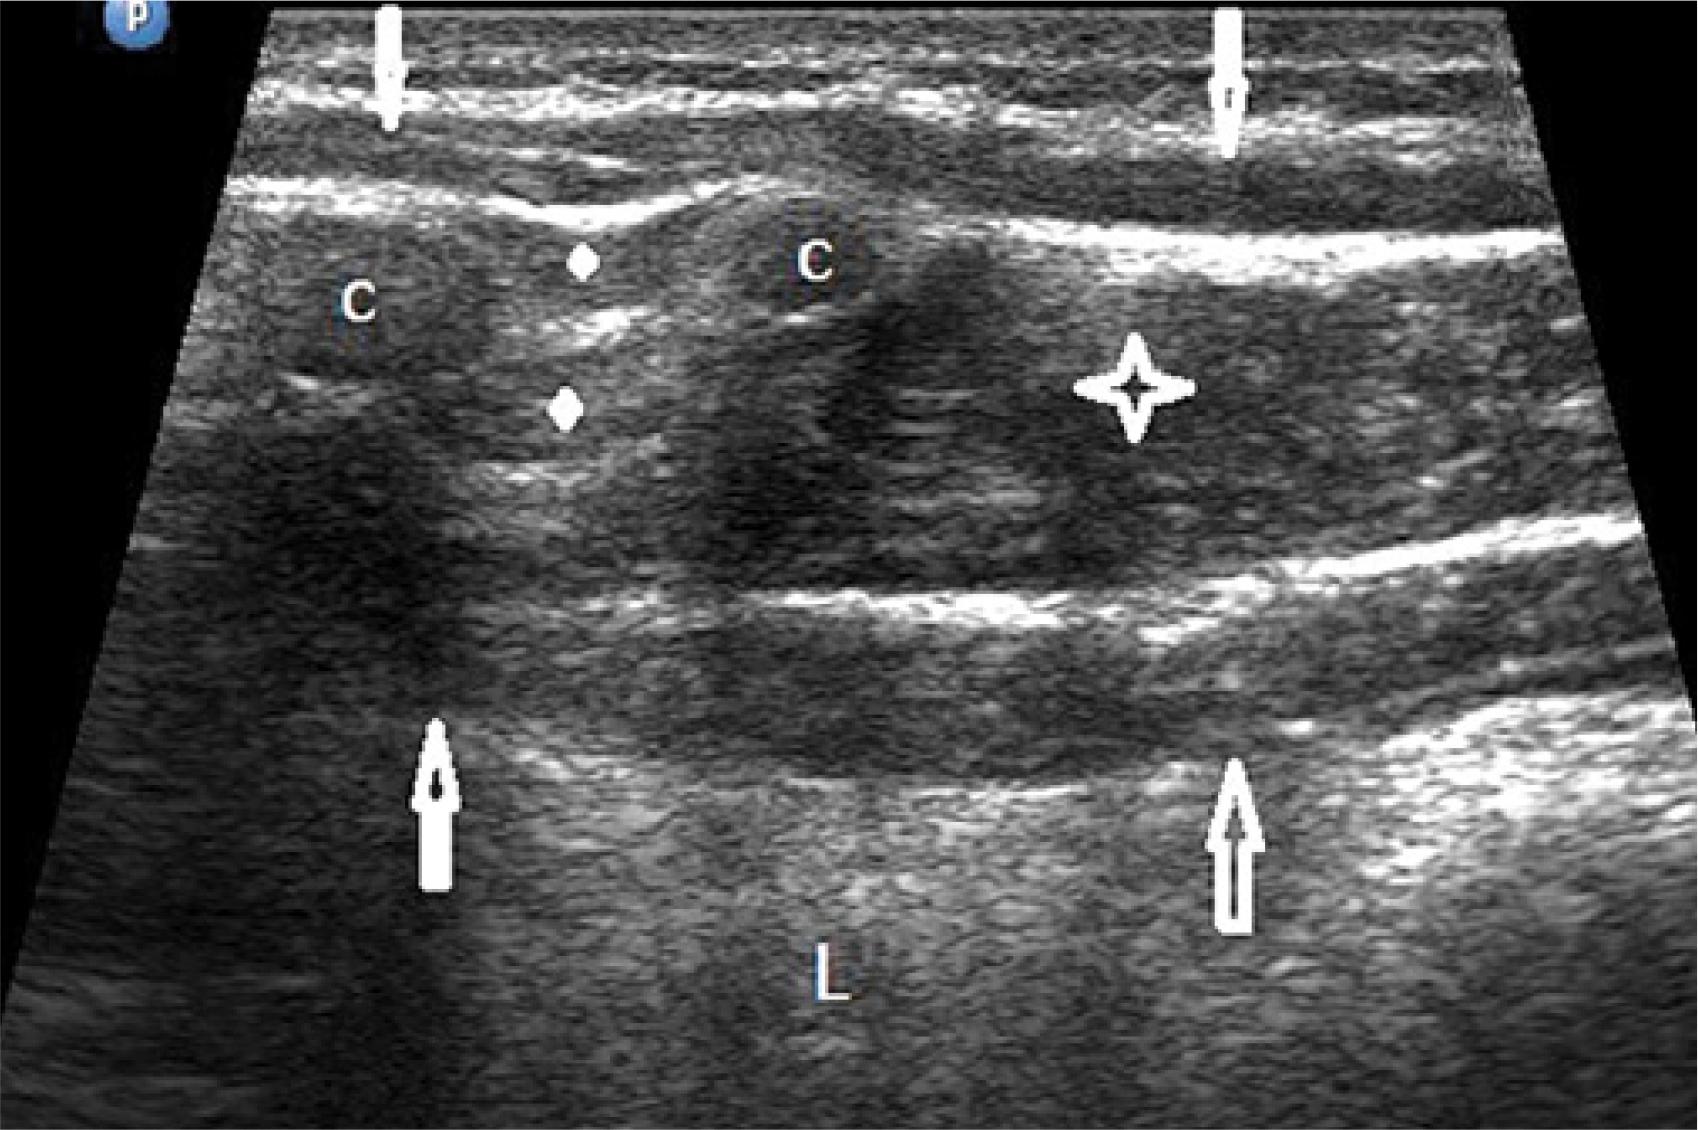

Ultrasonographic characteristics of the musculocartilaginous complex in 182 patients

| Heterogeneous | 121 | 66.5 |

| Hypoechoic | 35 | 19.2 |

| Hyperechoic | 26 | 14.3 |

| Smooth outline of indentation | 182 | 100.0 |

| Broad base of the costal arch | 182 | 100.0 |

| Focal costal compression | 152 | 83.5 |

| Segmental costal compression | 30 | 16.5 |